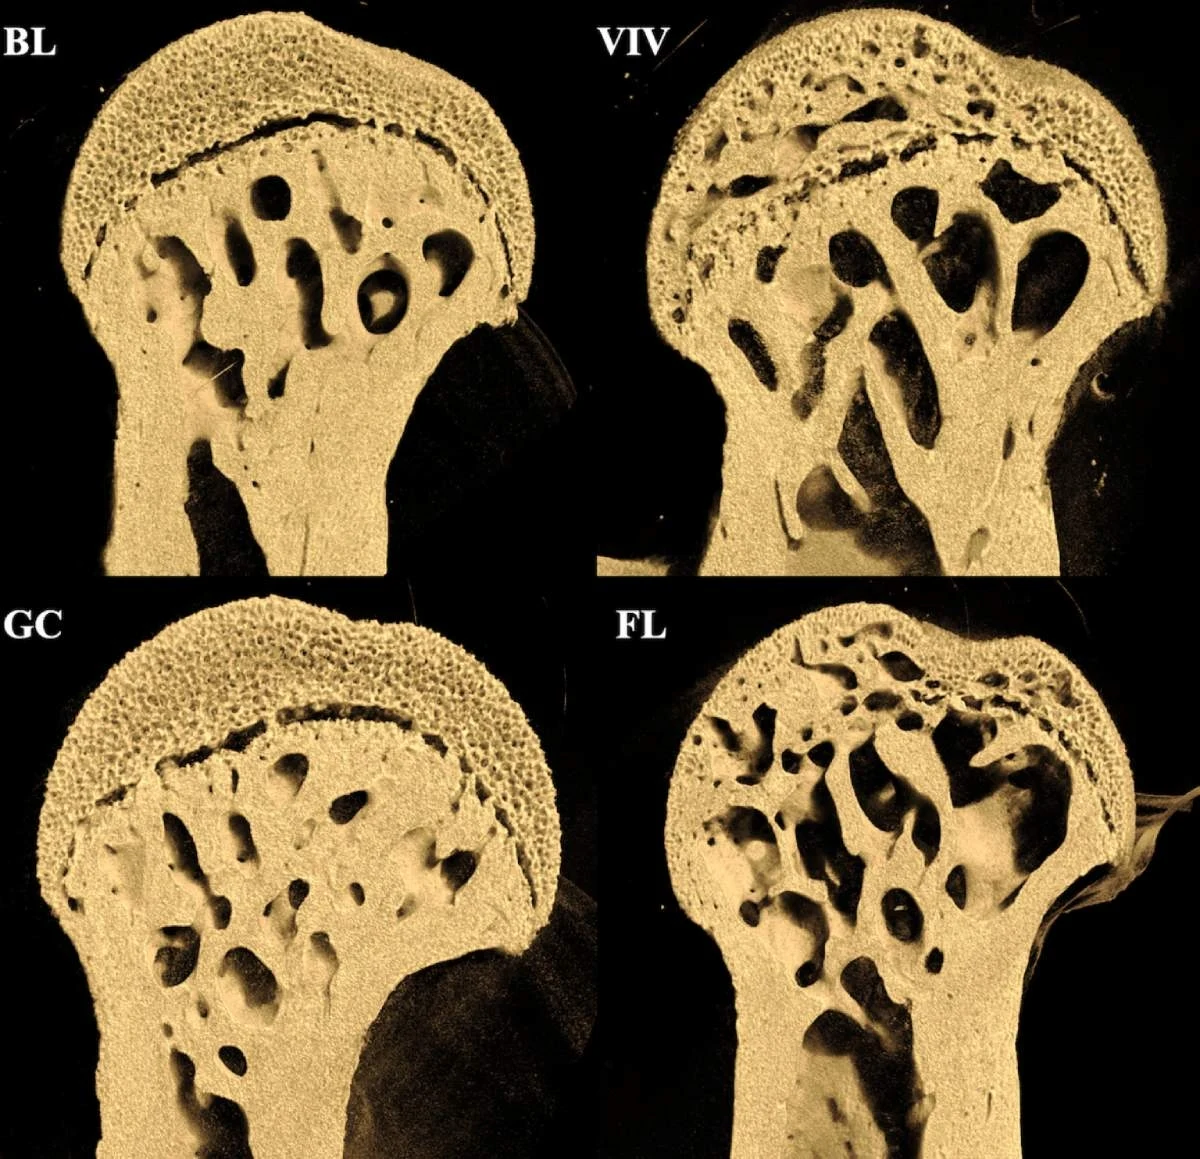

U myszy w kosmosie zaobserwowano duże dziury w kościach udowych, szczególnie tam, gdzie łączą się ze stawem biodrowym i kolanowym. Ich odcinek lędźwiowy kręgosłupa pozostawał jednak zadziwiająco nietknięty. Jak łatwo zauważyć, ta przyspieszona osteoporoza dotknęła obszary, które normalnie obciążone są masą ciała, nie zaś te, które wiążą się z pracą mięśni. Badanie sugeruje, że to z powodu mikrograwitacji. Nie znaleziono dowodów na niszczące działanie promieniowania kosmicznego na kości w tak krótkim okresie.

Gdyby utrata masy kostnej wynikała z promieniowania jonizującego, badacze spodziewaliby się raczej zobaczyć utratę zewnętrznych części kości i odsłonięcie wewnętrznej jamy szpikowej. Tak się jednak nie stało. U myszy zanik masy kostnej następował od środka. Na zdjęciach widać, że szyjka kości udowej pozostaje prawie nietknięta, za to widoczna jest utrata gąbczastego szpiku kostnego po 37 dniach w warunkach mikrograwitacji.